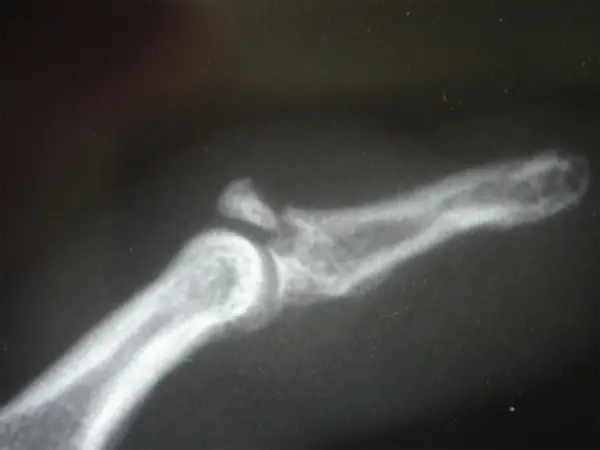

è quella situazione nella quale l’ultima parte di un dito (falange distale) rimane più o meno flessa. Questo atteggiamento è dovuto ad una lesione del tendine che fa estendere il dito (fig.1) oppure ad una frattura della parte dell’osso dove questo tendine si inserisce (fig. 2). Le cause possono essere legate sia ad una trauma importante, come durante l’attività sportiva, sia a situazioni banali quali il rimboccare le coperte. La diagnosi è prettamente clinica, ma è buona regola eseguire una radiografie per valutare se vi sia la presenza di un frammento osseo.